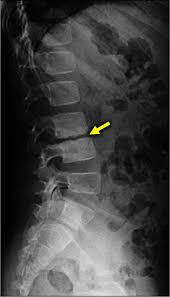

Redução do espaço discal L1 _ L2. Paciente deve trazer todos os exames de imagem realizados anteriormente.